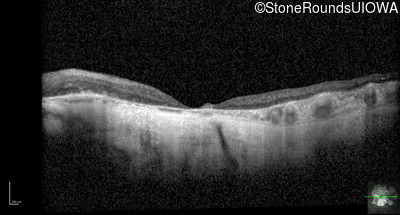

Optical Coherence Tomography - Right - 20/400 sc

Exemplar / OCT Stack

OCT Stack